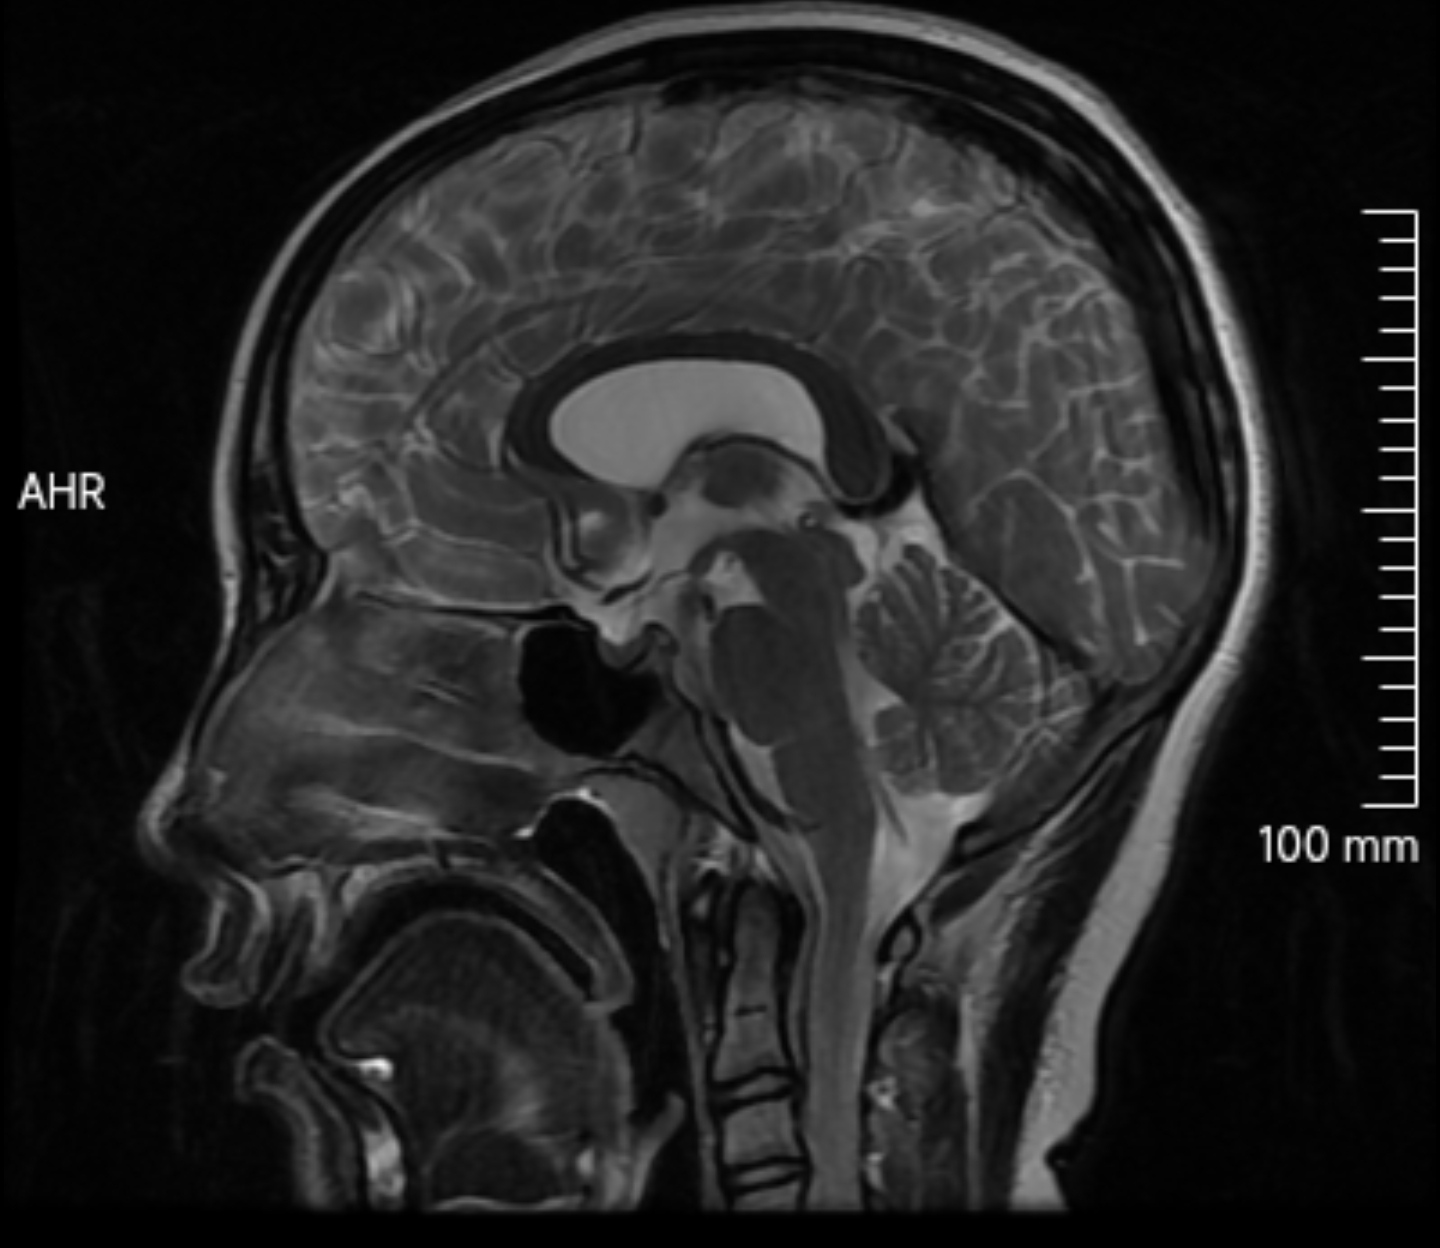

透明隔囊肿